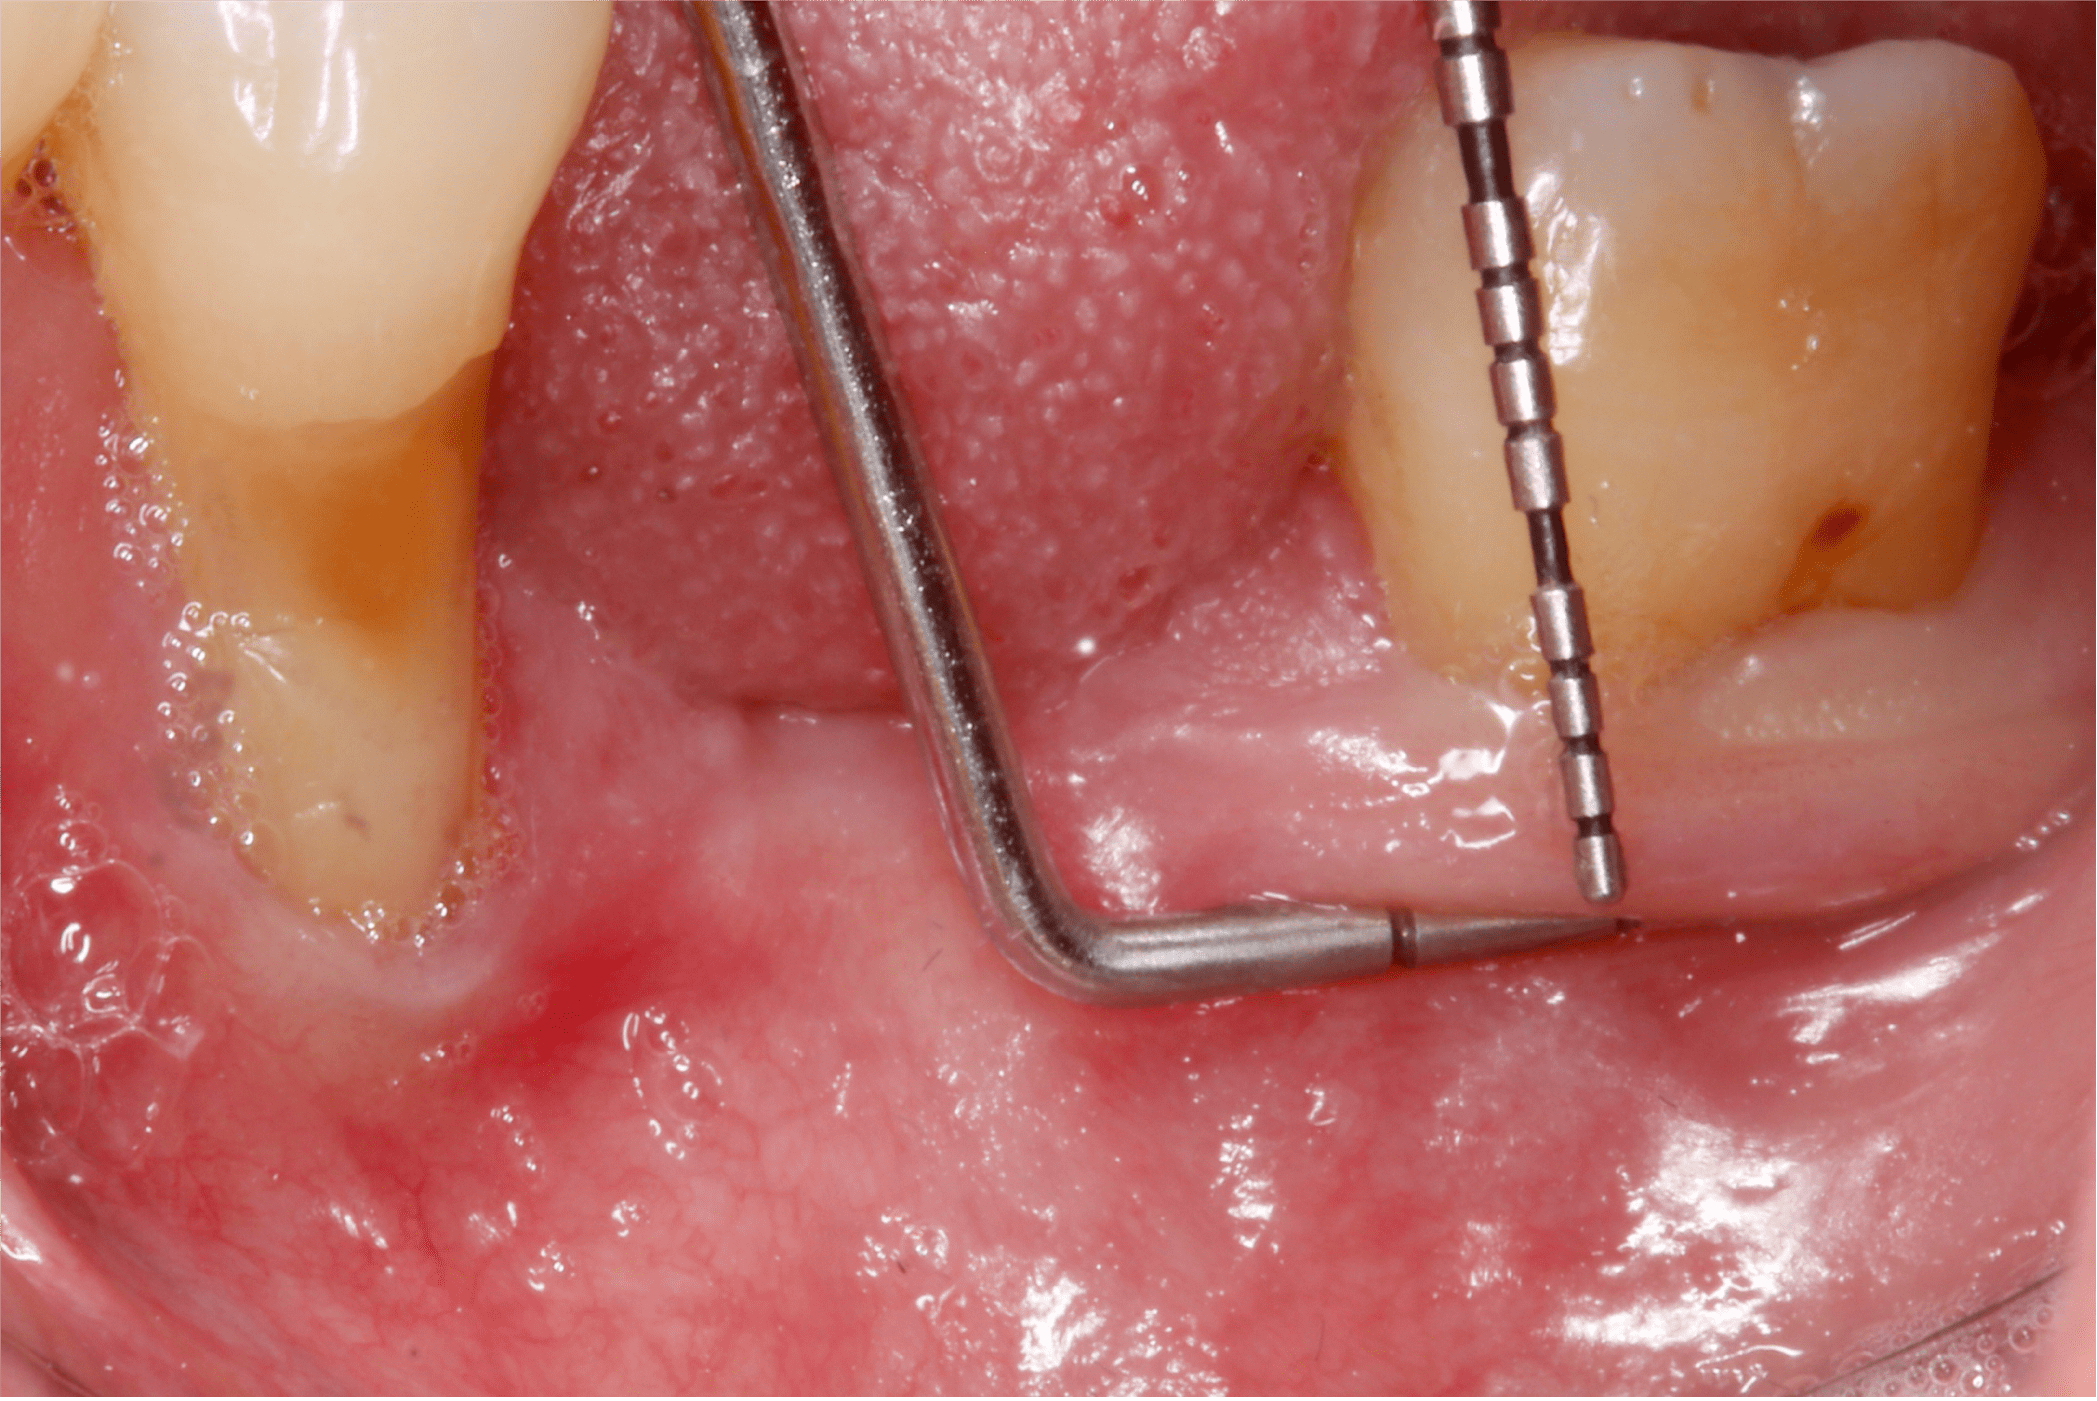

La examinación clínica reveló recesiones en múltiples órganos dentales y dos brechas edéntulas en la mandíbula correspondientes a los órganos dentales “36” y “46” las cuales fueron perdidas debido a caries (Fig. 2 y 3).

También se pudo apreciar que la paciente presentaba un fenotipo delgado y al medir la cantidad de encía queratinizada se observo una banda angosta de la misma, aproximadamente de 1 – 2 mm. (Fig. 4).

Tras un enjuague antiséptico, se anestesia la zona a tratar y se procede a preparar el lecho receptor por medio de incisiones de espesor parcial dejando periostio expuesto, esto con la intención de darle aporte vascular al injerto. (Fig. 6 y 7).

Fig. 3

Fig. 4

Fig. 6

Fig. 7